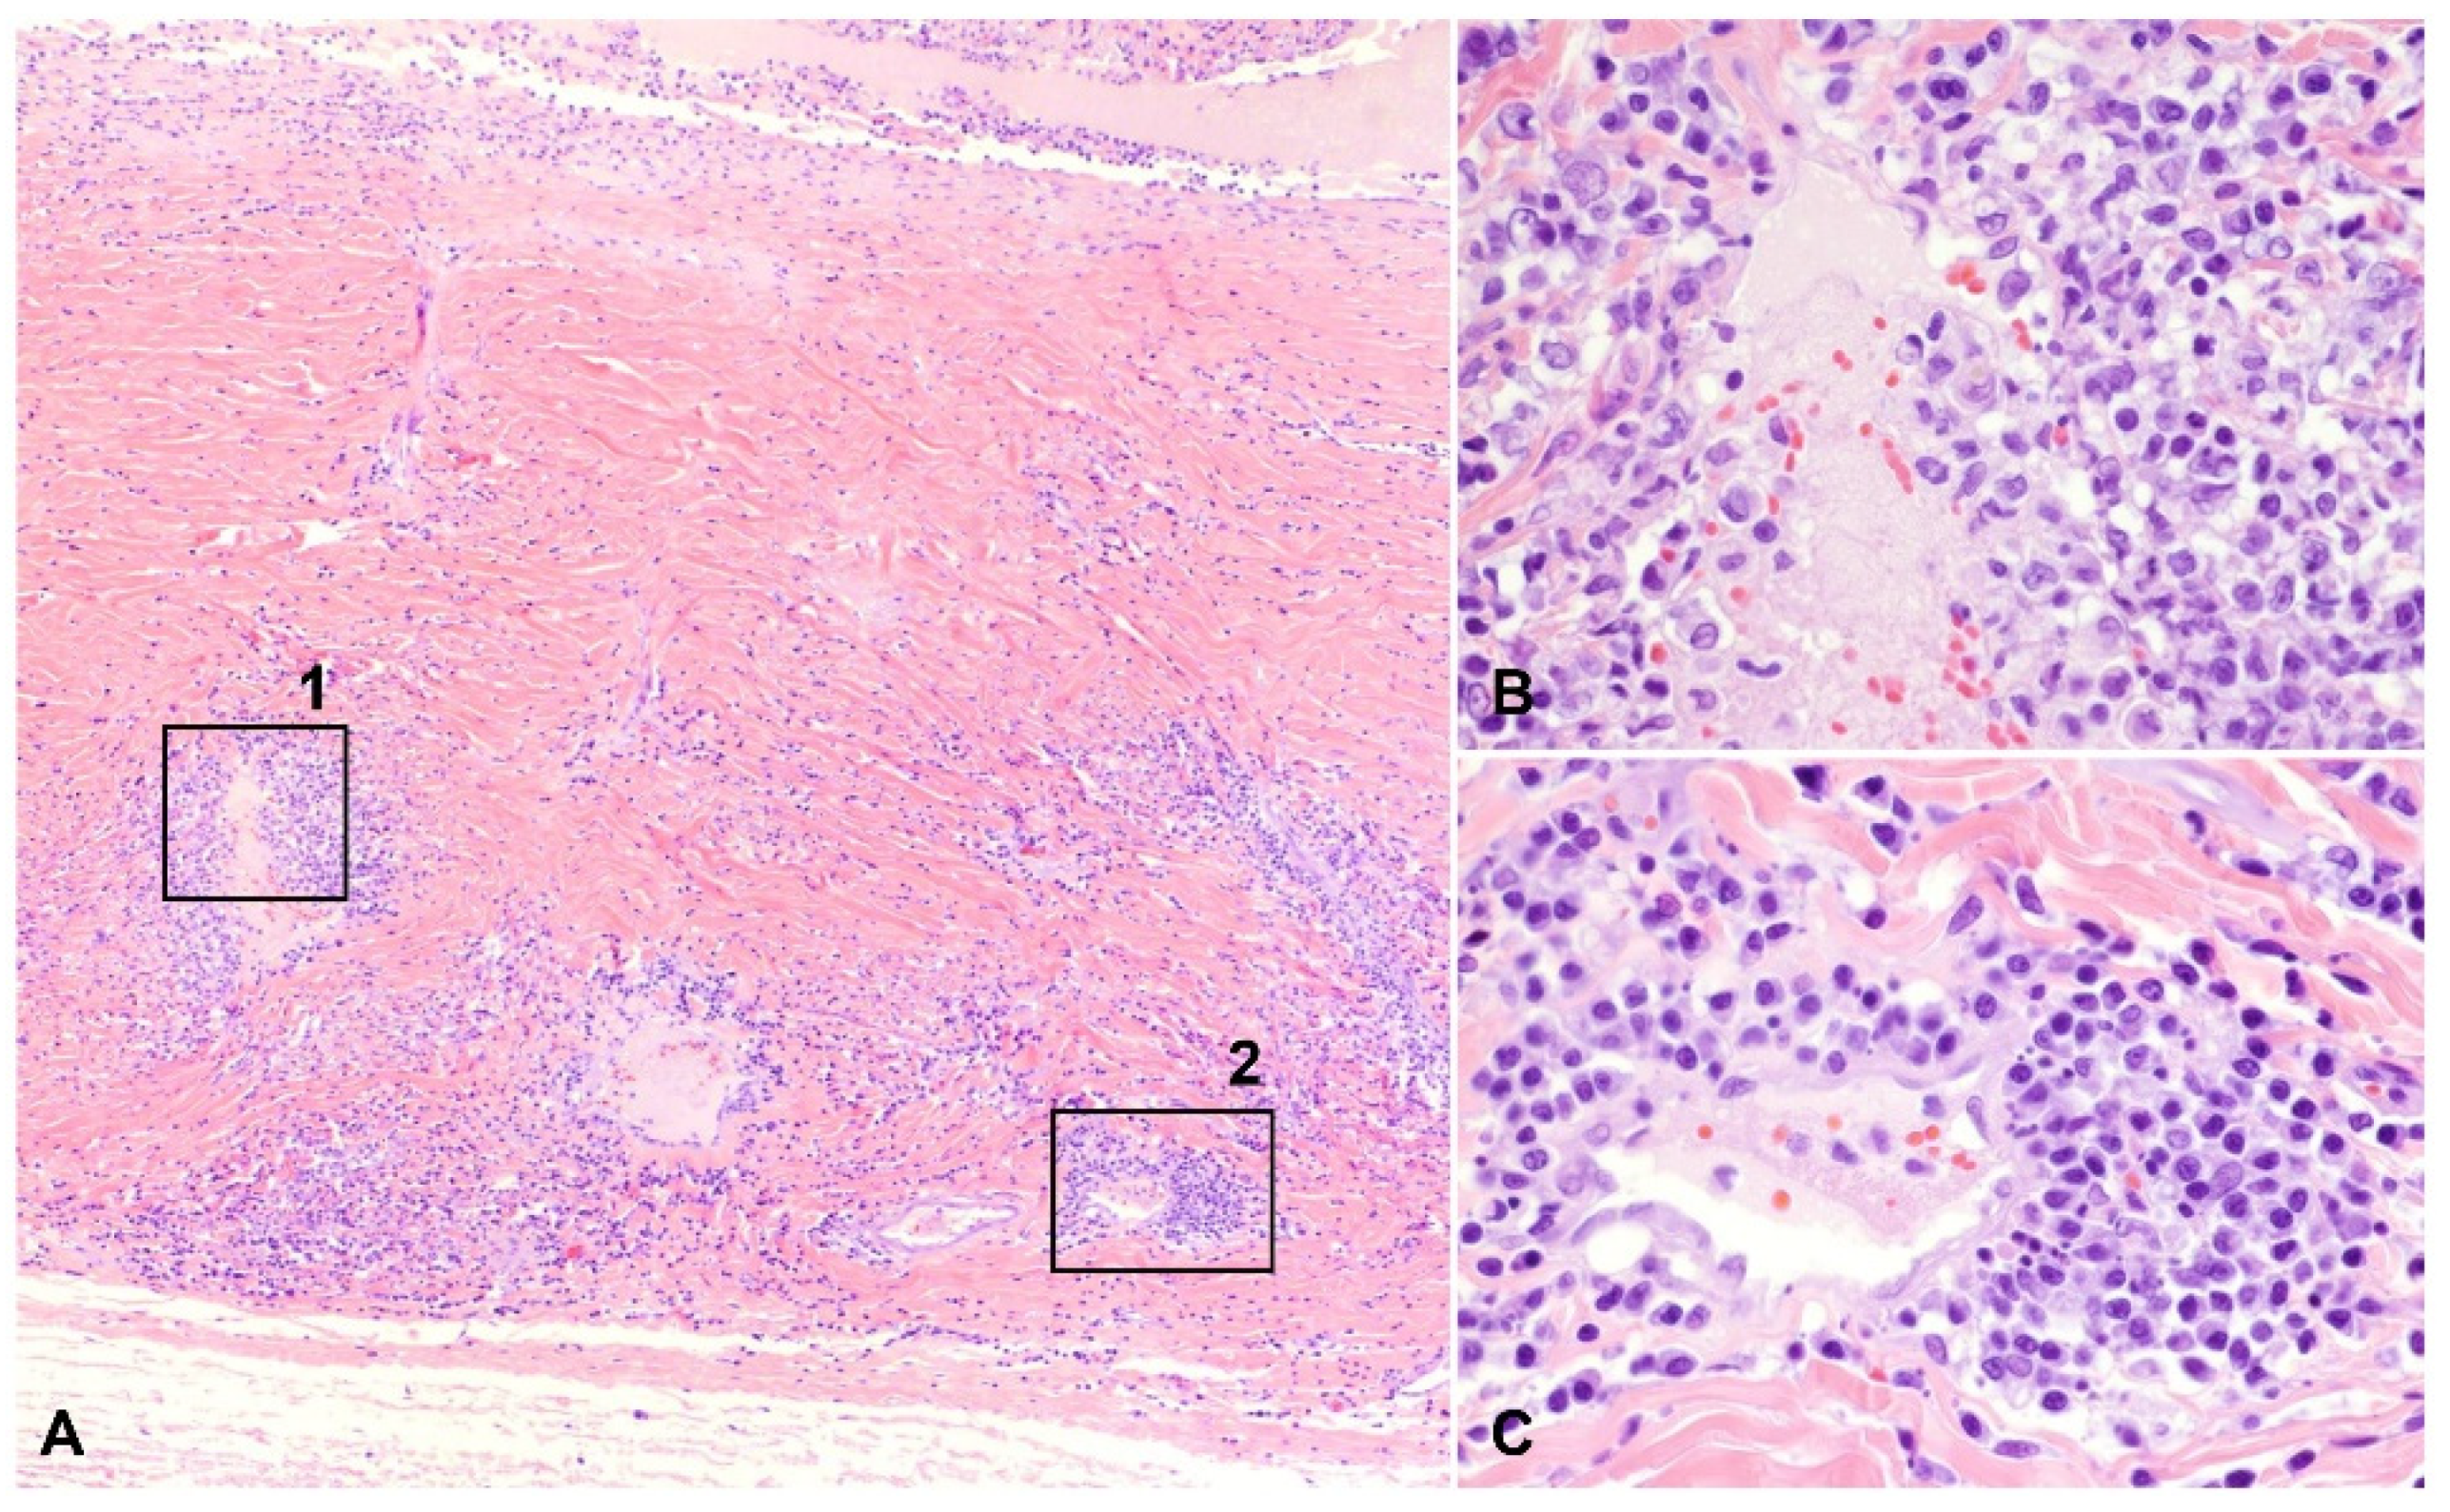

Figure 3.

Pyogranulomatous and plasmacytic scleral vasculitis, H and E: (A) inflammatory cells infiltrate the vascular wall and the surrounding stroma in the sclera (40× total magnification); (B) mural and perivascular pyogranulomatous infiltration, magnified from squared area 1 noted on (A) (400× total magnification); (C) plasmacytic infiltration centered on a blood vessel, magnified from squared area 2 noted on (A) (400× total magnification).

A total of 9 of the 30 cases (30.0%) had vasculitis, 8 of which consisted of pyogranulomatous infiltration of the vessel wall (Figure 3 and Figure 5), with the remaining cases characterized by plasmacytic infiltrate (Figure 6). Regardless of the infiltrate, all lesions of vasculitis included fibrinoid degeneration of the vessel walls, with plump activated and/or necrotic endothelial cells. Vasculitis was noted in the episcleral vessels in five cases: in the choroid, ciliary body, and retina in four cases each and in the iris in two cases.